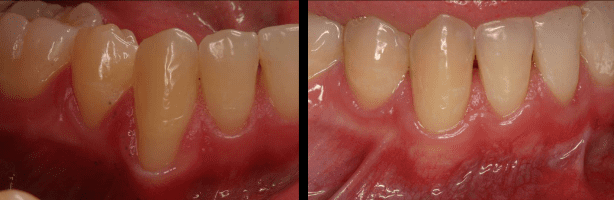

تُستخدم هذه التقنية لعلاج انحسار اللثة وتغطية جذور الأسنان المكشوفة باستخدام أنسجة لثوية ذاتية أو تقنيات زراعة حديثة.